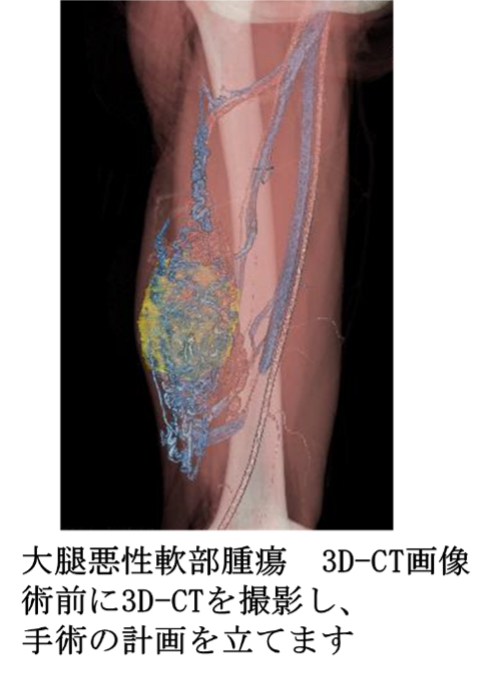

悪性腫瘍広範切除術

肉腫の手術は広範切除術が基本となります。肉腫は周囲の組織に目に見えない微小浸潤をしていることが多く、腫瘍だけを切除すると周囲から再発する確率が高いため、腫瘍を周囲の正常組織で覆って切除する“広範切除”が必要です。広範切除後の組織欠損に対して人工関節や骨移植、植皮、筋皮弁などを用いた再建が必要になることがあります。組織再建は皮膚科や形成外科と協力して行っております。